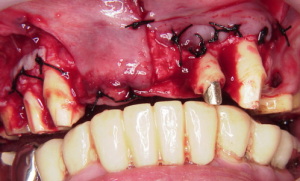

進行した歯周病の改善症例

初診です。

歯周病が進行し前歯が出てしまい

口を閉じることが出来ません。

残念ながら前歯のいくつかはぐらぐらなので

抜歯せざるを得ませんでした。

抜歯と同時に腫れている歯茎を切り取ります。

前歯にブリッジタイプの仮歯を入れます。

腫れた歯茎がなくなりますが

このままではへこみが出来ていしまいます。

そのままブリッジを入れると

長さが不均一になる事を

仮歯でテストします。

仮歯で隠して行っています。

歯茎の強化と審美的な回復を

一度の手術で行います。

仮歯を戻します。

歯茎にボリュームが出たので仮歯を押し付けて

今度は歯茎に窪みを造ります。

まだ仮歯ですがこの形で仕上げていきます。

下の奥歯はほとんどがインプラントです。

治療完了です。